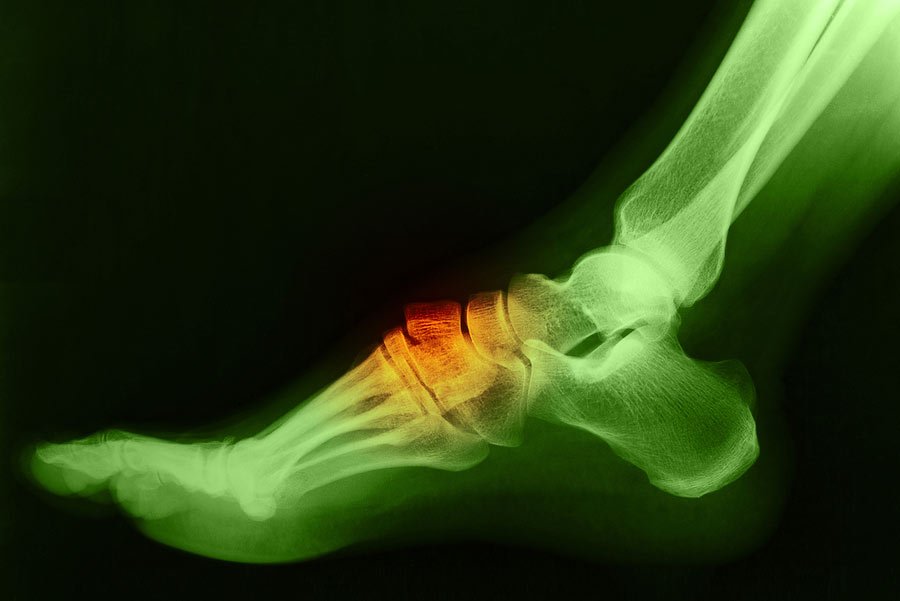

Foot & Ankle Replacement

Coming Soon